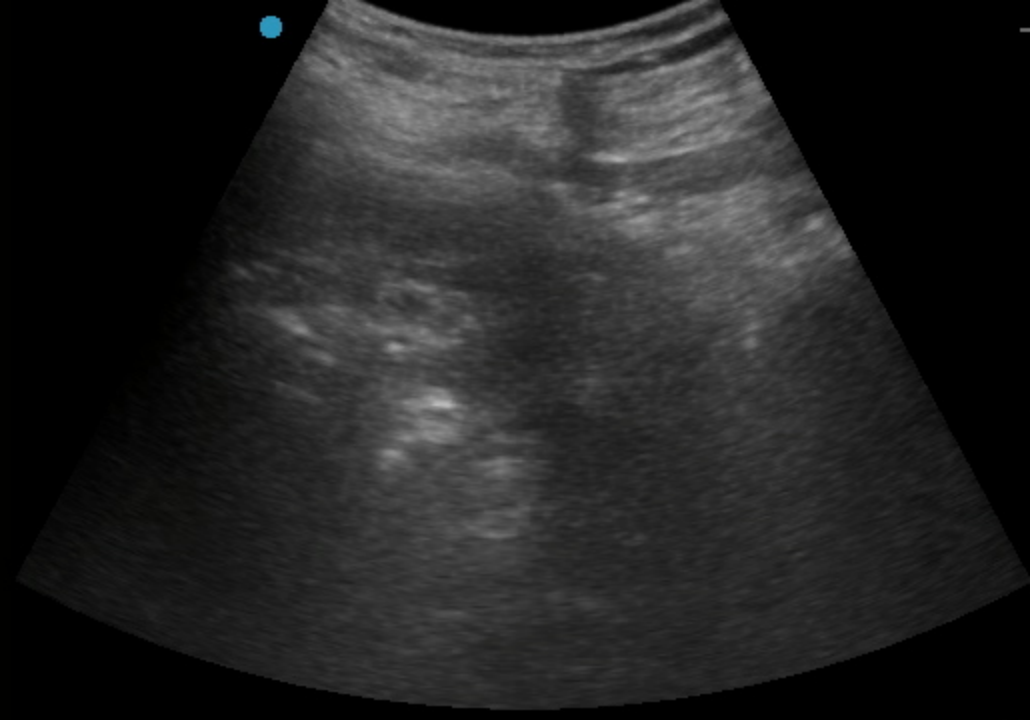

按照许主任本人通俗的说法,这是典型的手术指征明确、但病人基础条件恶劣的病例。对于麻醉提出了极大的挑战;由于患者透析以及下肢血栓抗凝的需要,下肢手术常用的椎管内麻醉出血风险太大,无法进行。而采用全身麻醉,患者肾衰以及心脑血管风险又会给围术期管理带来极大挑战。通过术前详细的评估,许主任最终决定对该患者实施单纯神经阻滞麻醉。考虑到抗凝带来的出血风险,优化了神经阻滞入路,采用了对凝血功能要求相对低的超声引导下前路腰丛+骶旁坐骨神经联合阻滞,精准覆盖术区,患者在清醒但完全无痛的状态下顺利完成手术,术后直接转回普通病房。同时,神经阻滞镇痛效果会持续十余个小时,也解决了术后镇痛问题。